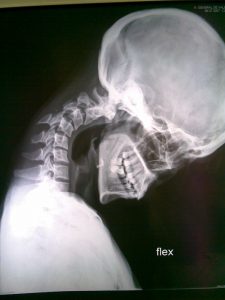

Cifosis postquirúrgica en RX dinámicas. En algunos casos existe dificultad para mantener la mirada al frente: como puede observarse en la segunda imagen. La extensión forzada de manera continua agota la musculatura y genera dolor e incapacidad, más evidente al final del día.